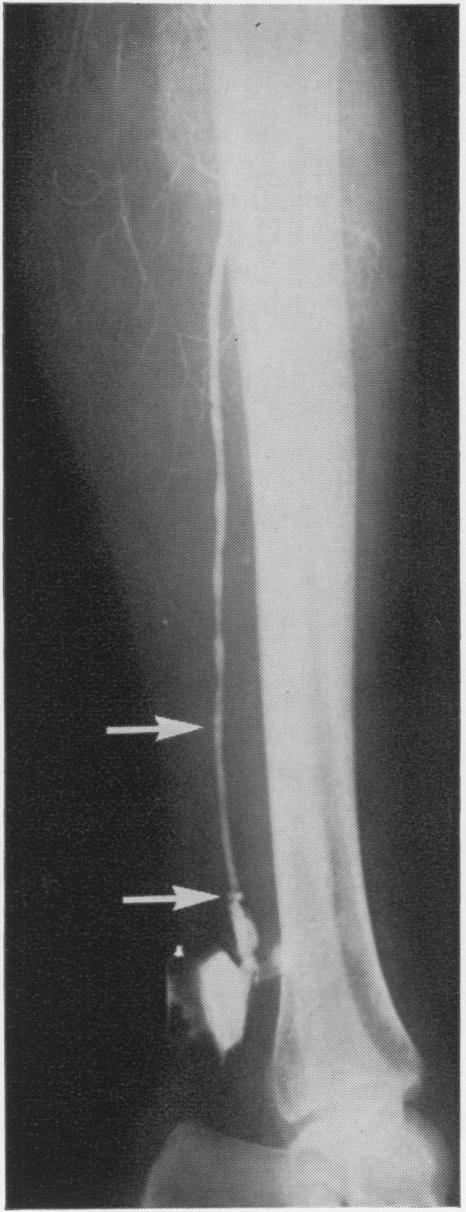

Arterial injuries secondary to the use of the Fogarty catheter.

Ann Surg. 1970 Jun;171(6):971-8. doi: 10.1097/00000658-197006010-00019.